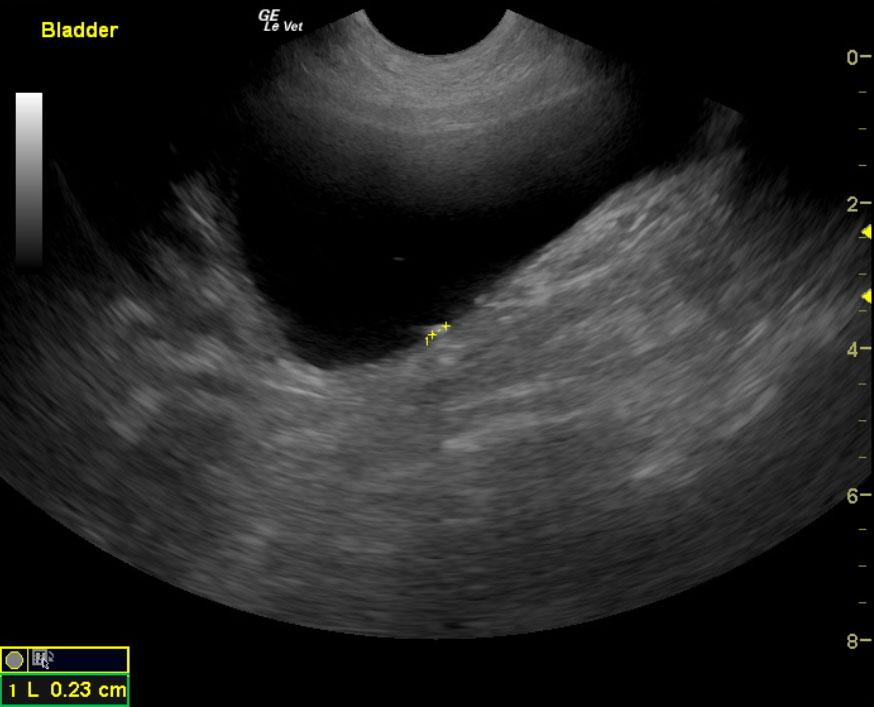

The kidneys in this patient had a persistent, slightly irregular contour, with the left kidney demonstrating slight pyelectasia (0.26 cm). The urinary bladder, trigone and pelvic urethra presented normal wall thicknesses with anechoic urine and normal tone. The urinary bladder revealed slight calculus at 0.23cm, yet was not shadowing. No evidence of inflammatory or neoplastic changes were noted.